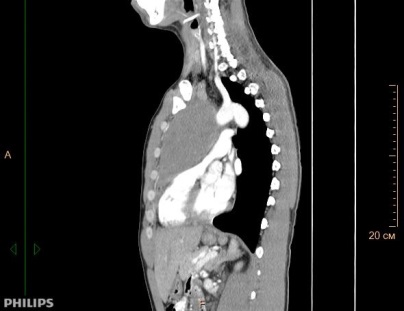

При поражении органов средостения рентгенологическая и клиническая картина неспецифичны (рис.1), только развернутый гистологический диагноз позволяет определиться с тактикой и подобрать эффективную терапию.